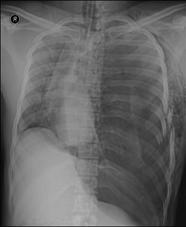

TRAUMATISME TORACICE

Pneumotorace sufocant bilateral Pneumotorace sufocant stang

Pneumotorace

sufocant stang Pneumotorace

sufocant drept Pneumotorace

sufocant drept